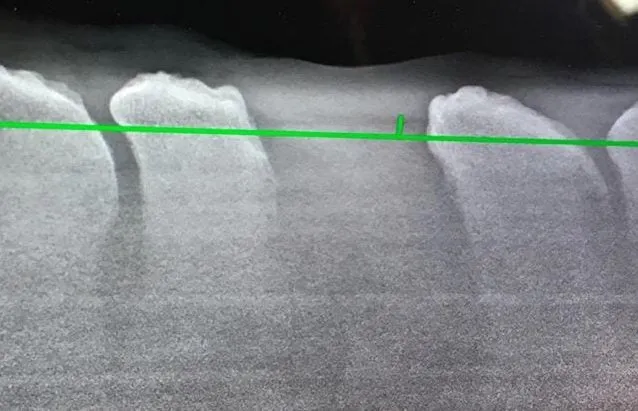

Afterwards, the owner had to clean the wound daily, and the stitches were removed by the veterinarian after a week. The horse was kept in a stall and given painkillers, but was walked once or twice a day. After a few weeks in the stall, the horse was moved to a small sick paddock. It was important that the horse didn't roll over. Fortunately, this wasn't an issue. In the image below, you can see an X-ray of the horse's back post-surgery.